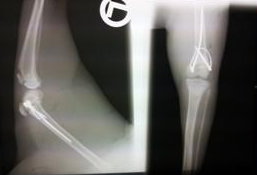

• Knochenchirurgie

Unser Ziel ist es mit Hilfe der „biologischen Osteosynthese-BO“

ein optimales Ergebnis zu erreichen

Sinn der BO ist es mit Drähten und Stäben die natürlichen Heilungsvorgänge im Knochen möglichst wenig zu stören. Unsere neue Methode, von einem österr. Tierarzt entwickelt, bietet zudem eine kostengünstige Alternative zur bisherigen Plattentechnik an.

Bei der Katze schon seit 2011 unsere beliebte Art der Frakturversorgung. Die Tiere mussten nur daran gehindert werden nach 2 Tagen wieder auf Bäume zu klettern.

Der frühe funktionelle Gebrauch und die zunehmende Belastung der operierten Extremität bei den mit Paraossärer Klammer-Cerclage-Stabilisierung versorgten Patienten, wird als Beweis für die ausreichende Stabilität und geringe Schmerzbelastung der Methode im Sinne einer „biologischen“ Osteosynthese angesehen.

Kostengünstige Alternative zu herkömmliche Fixationsmethoden in der Knochenchirurgie